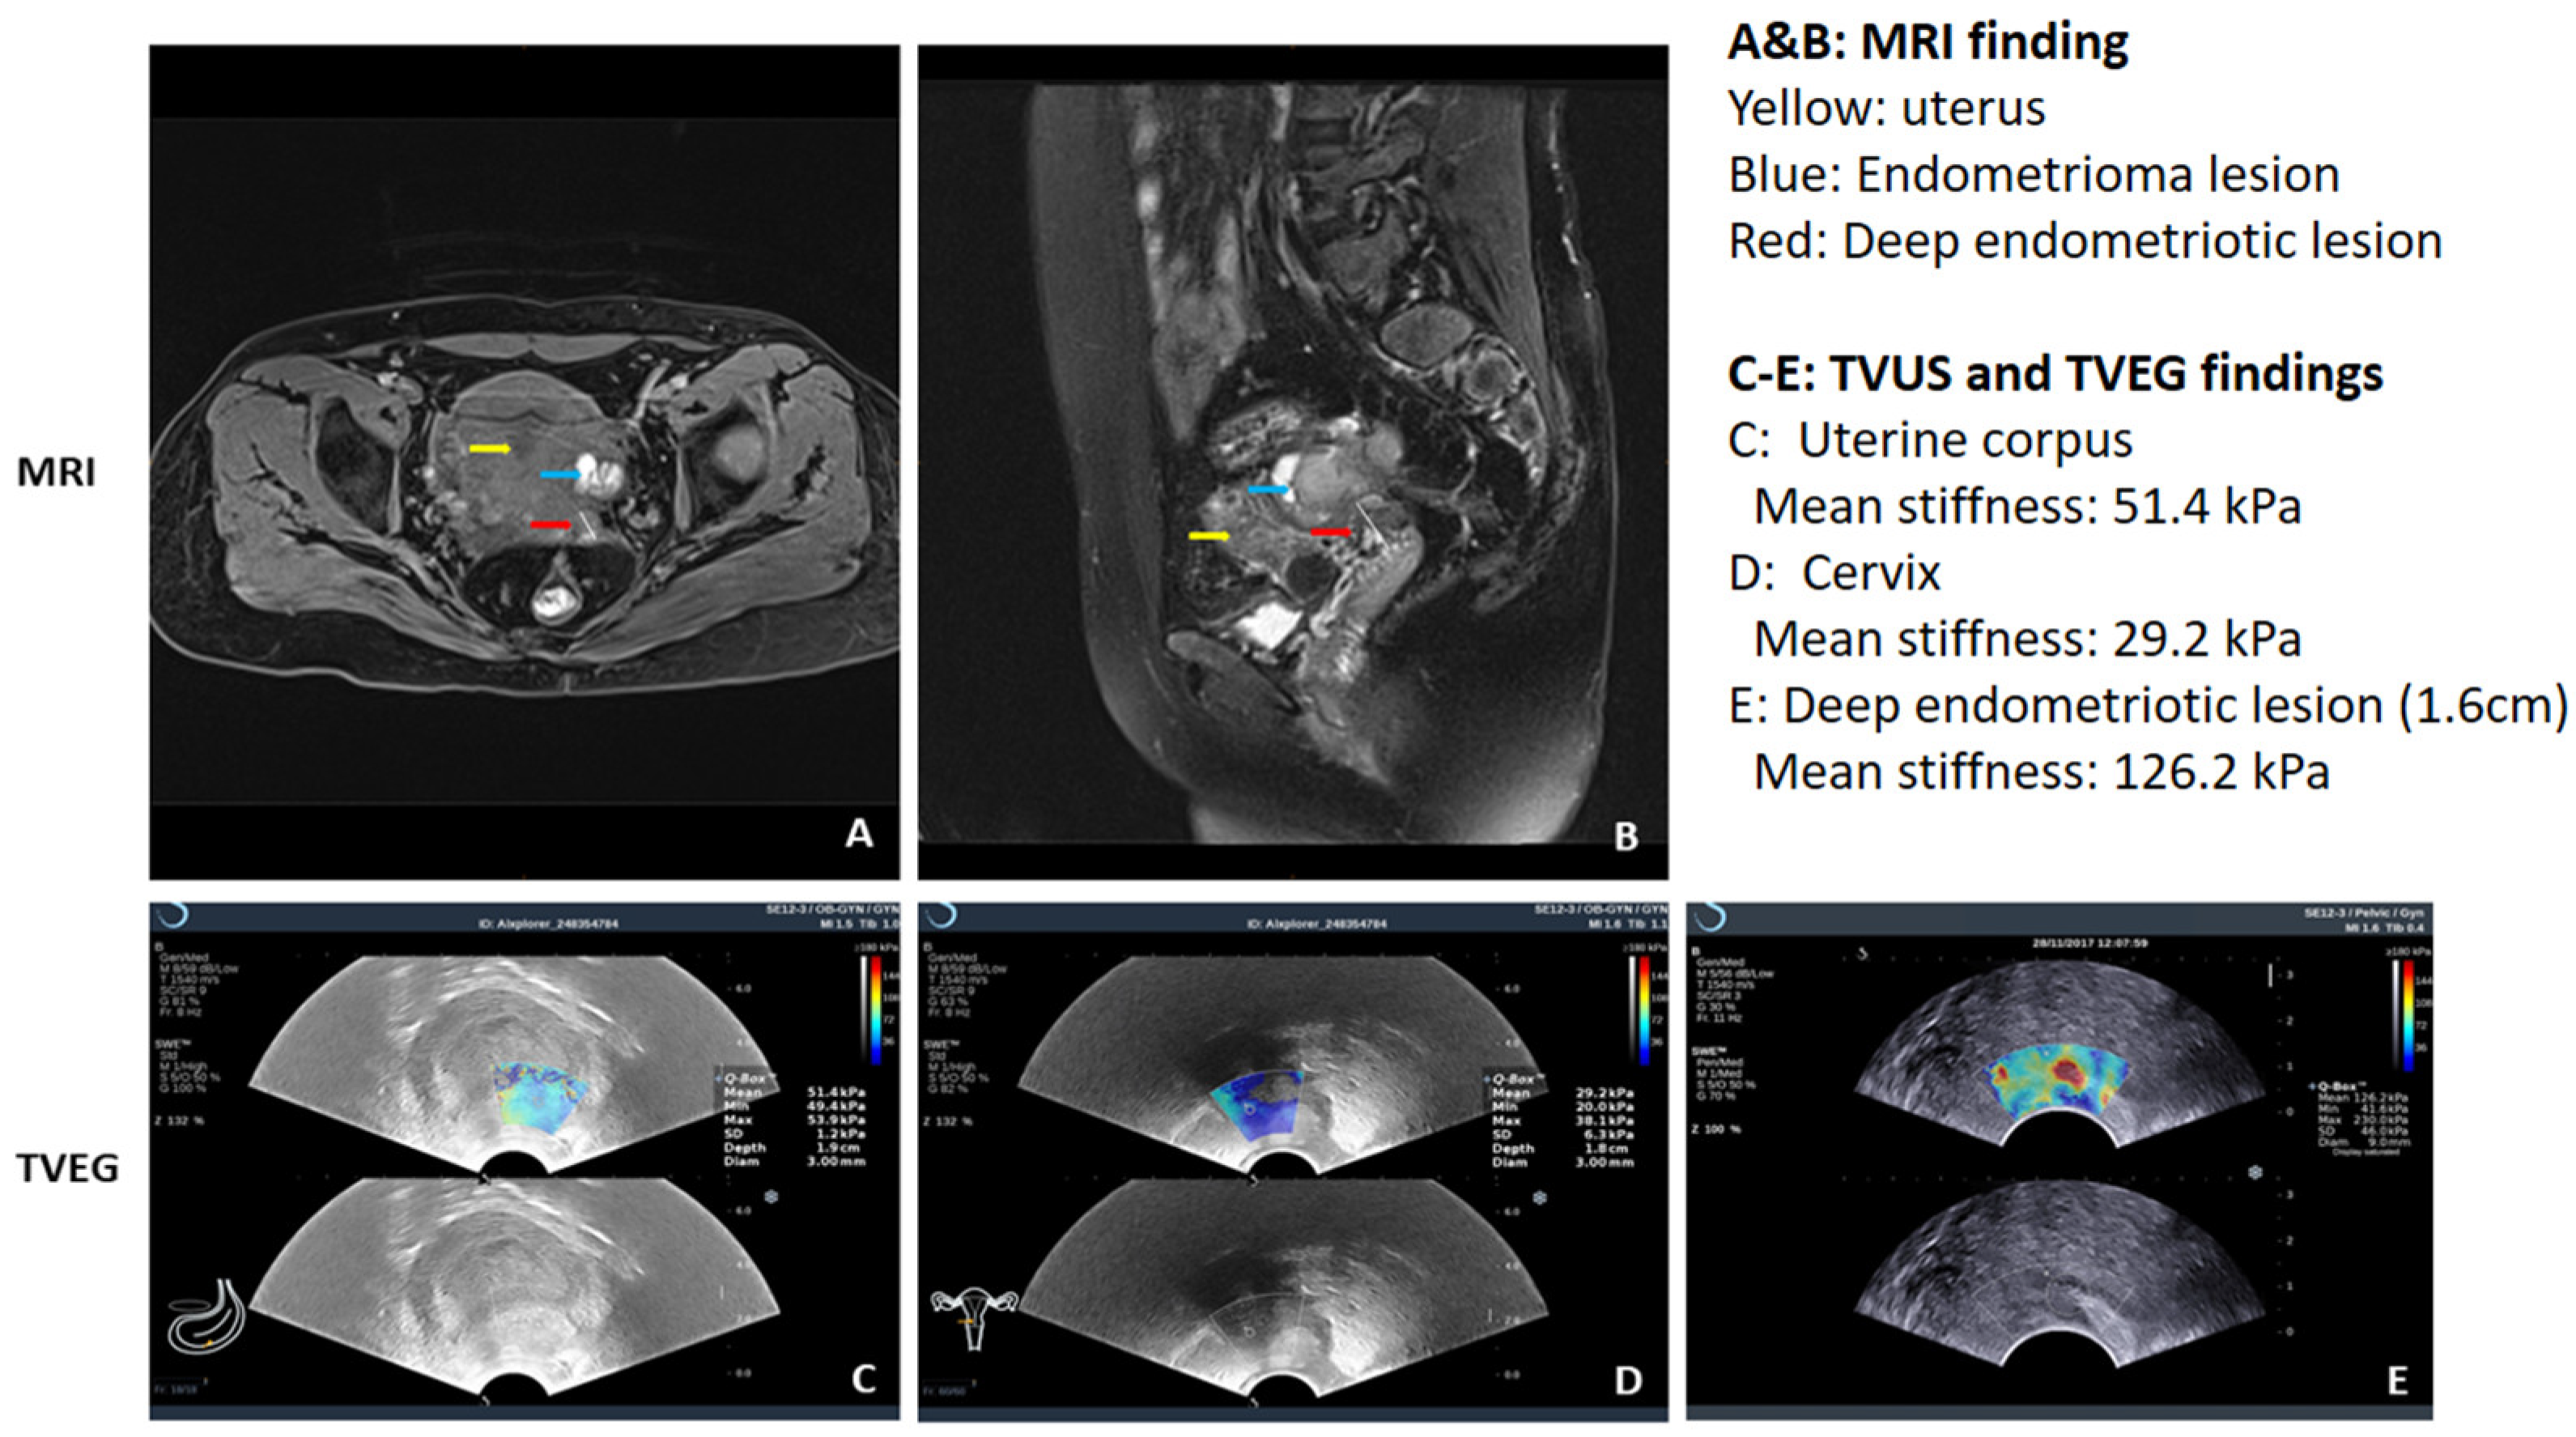

- Ding, D.; Chen, Y.; Liu, X.; Jiang, Z.; Cai, X.; Guo, S.W. Diagnosing Deep Endometriosis Using Transvaginal Elastosonography. Reprod. Sci. 2020, 27, 1411–1422. [Google Scholar] [CrossRef]

- Liu, X.; Ding, D.; Ren, Y.; Guo, S.W. Transvaginal Elastosonography as an Imaging Technique for Diagnosing Adenomyosis. Reprod. Sci. 2018, 25, 498–514. [Google Scholar] [CrossRef]